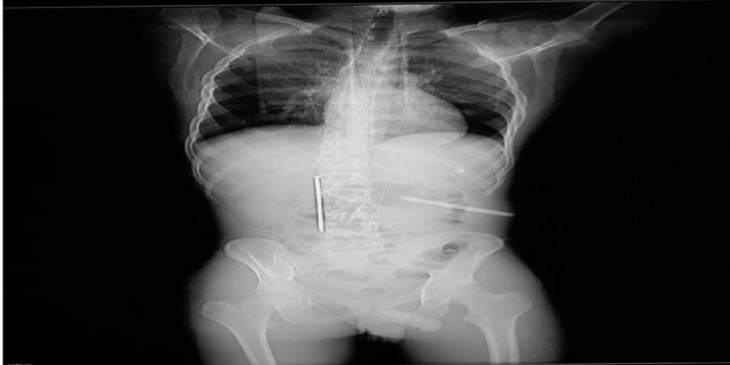

တ႐ုတ္ႏိုင္ငံအေရွ႕ပိုင္း၊ နင္းဘိုၿမိဳ႕မွာ အမ်ိဳးသားတဦးဟာ အေလာင္းအစားနဲ႔ ၁၂ စင္တီမီတာ အရွည္ရွိတဲ့ သံေခ်ာင္းကို မ်ိဳခ်ခဲ့ပါတယ္။

ဂြန္းအမည္ရတဲ့ အဲဒီအမ်ိဳးသားဟာ ယြမ္ေငြ ၆၀၀၀ အႏိုင္ရဖို႔အတြက္ သံေခ်ာင္းကိုမ်ိဳခ်ဖို႔ အေလာင္းအစား လုပ္ခဲ့တာလို႔ တ႐ုတ္ျပည္သူ႔ေန႔စဥ္သတင္းမွာ ဒီဇင္ဘာ ၃ ရက္ေန႔က ေဖာ္ျပပါတယ္။

အဲလိုမ်ိဳခ်ခဲ့ၿပီး ရက္အနည္းငယ္အၾကာမွာေတာ့ သံေခ်ာင္းဟာ အစာအိမ္ကို ထိုးမိခဲ့ၿပီး ေသလုေမ်ာပါးေ၀ဒနာ ခံစားခဲ့ရတာပါ။

ခုခ်ိန္မွာေတာ့ ဂြန္းရဲ႕ကိုယ္ခႏၶာထဲက သံေခ်ာင္းကို ဆရာ၀န္က ထုတ္ယူေပးႏိုင္ခဲ့ၿပီး ခြဲစိတ္မႈ ကုန္က်စရိတ္ဟာ ယြမ္ေငြ ၁၀၀၀၀ ေက်ာ္ က်သင့္ေစခဲ့တယ္လို႔ သတင္းမွာ ေဖာ္ျပပါတယ္။